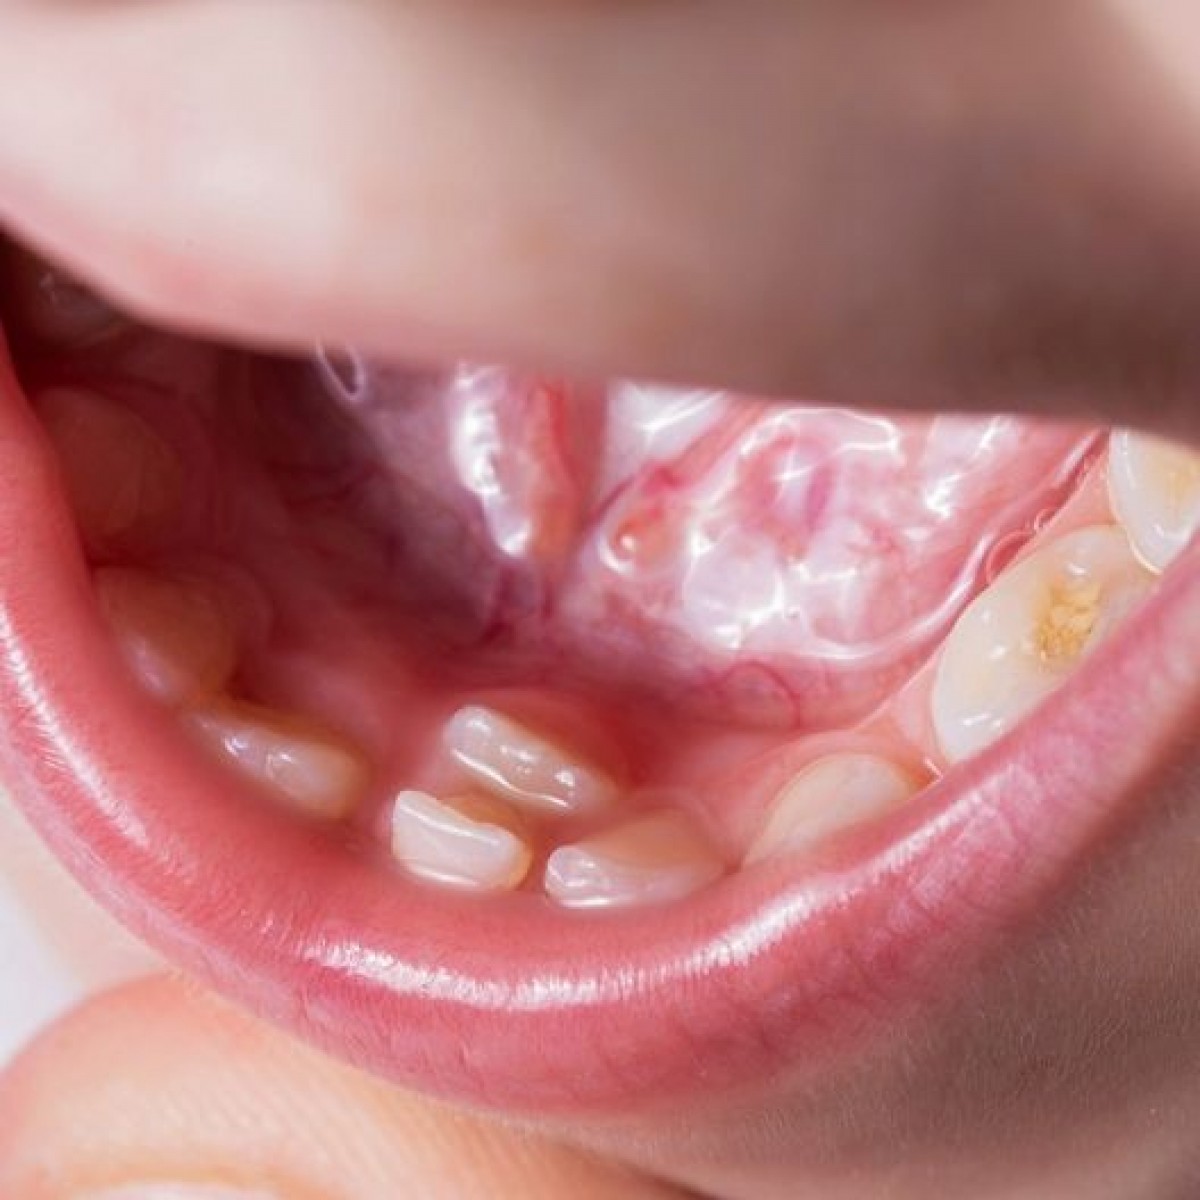

This clinical case report describes concomitant developmental disorders in the permanent dentition. The concurrence of bilateral dens evaginatus and dental fusion is a rare dental anomaly. Dental fusion is characterized by the union of 2 adjacent teeth at the crown level, which produces the formation of an enlarged clinical crown.

Dens evaginatus is an enamel elevation similar to a cusp, generally located in the main groove of molars and premolars. The etiology of both anomalies is uncertain. The purpose of this paper was to review the related literature and present a clinical case where both anomalies are present.